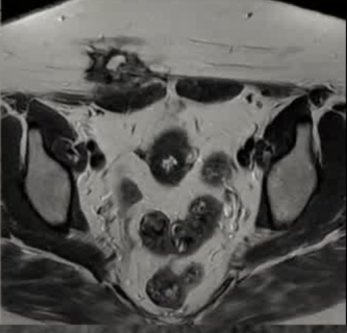

病灶位置:16个疼痛性目标病灶位于脐部(7/16,43.8%)、膈肌(4/16,25.0%)、腹股沟管(3/16,18.8%)和子宫肌肉层(即腺肌症,2/16,12.4%)。

病灶大小:目标病灶的最大直径中位数为19毫米(四分位距13-22.3)。

影像引导方式:超声和横断面成像(CT或MRI)结合是最常用的影像引导方式(10/16,62.5%)。

保护措施:几乎所有干预都需要辅助保护措施,其中水分离术(13/16,81.3%)和水分离术与温盐水填充手套的皮肤保护结合(9/16,56.3%)是最常见的保护措施。